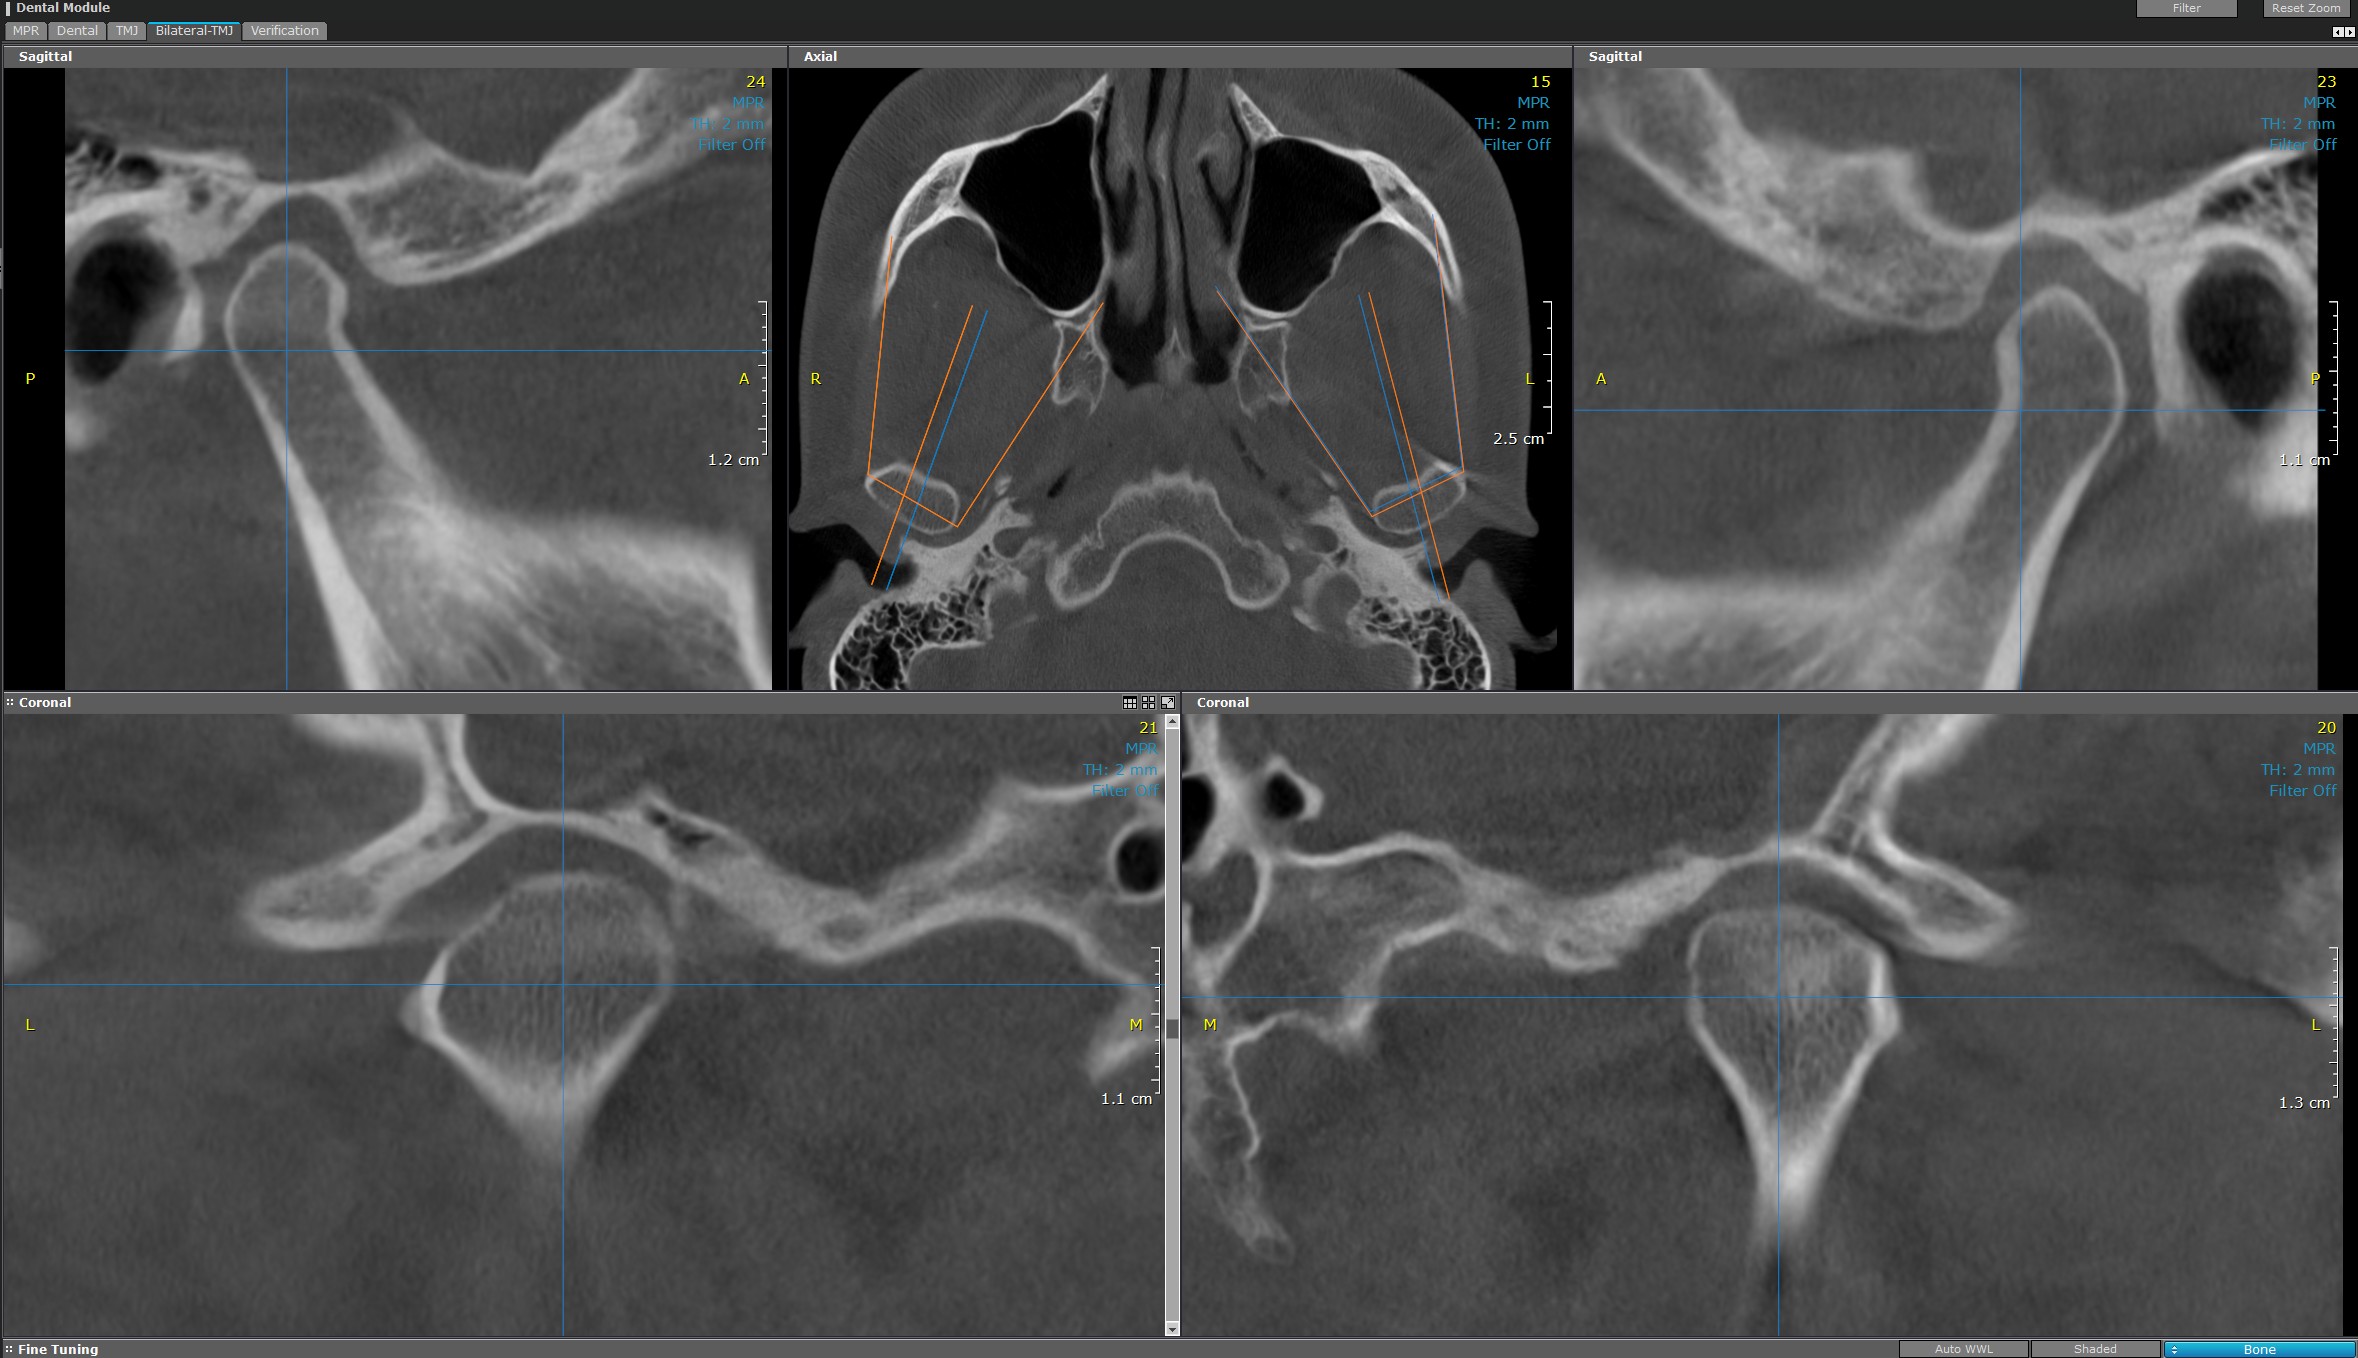

CT ATM (Articulații temporo-mandibulare)

CT-ul pentru articulații temporo-mandibulare (ATM) utilizează tehnologie avansată pentru a oferi o perspectivă detaliată asupra complexului articular mandibular. Investigația este esențială în evaluarea și planificarea tratamentului de specialitate. Imaginile referitoare la forma și structura articulației temporo-mandibulare sunt clare și precise.

Sunt generate informații importante referitoare la discurile articulare și țesuturile moi din jurul articulației. Cu o rezoluție înaltă și capacitate de scanare rapidă, CT ATM permite diagnosticarea precisă a afecțiunilor, disfuncțiilor, fracturilor sau a altor patologii articulare.